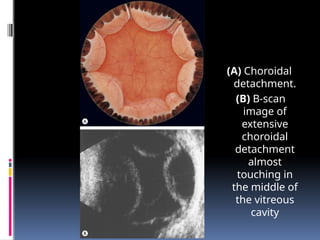

(A) Choroidal

detachment.

(B) B-scan

image of

extensive

choroidal

detachment

almost

touching in

the middle of

the vitreous

cavity